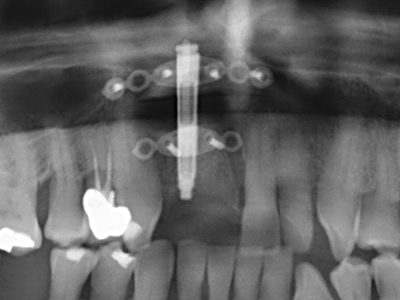

En la extracción de bloques óseos la piezocirugía también presenta ventajas adicionales: Además de la alta precisión en la osteotomía que ya se ha descrito antes, se ha comprobado que el uso de los delgados insertos de sierra resulta especialmente cuidadosas con el hueso. Frente a esto, sobre todo cuando se usan las fresas de Lindemann, cabe esperar pérdidas en la extracción significativamente más altas debido al mayor grosor de la parte frontal del cabezal (Lakshmiganthan, Gokulanathan et al. 2012). La separación basal que se necesita en particular en los injertos de bloque extraídos de forma retromolar se ve facilitada mediante sierras perpendiculares especialmente previstas a tal fin, lo que permite considerar que la cirugía piezoeléctrica es un procedimiento preciso y seguro para la obtención de bloques de hueso en el área retromolar (Happe 2007) (fig. 1-12).

El tejido óseo no solo tiene un contenido puramente mineral, sino que también presenta una importante proporción de fibras de colágeno. Esto no solo garantiza una buena resistencia a la presión, sino también una cierta flexibilidad, que puede aprovecharse para la realización de aumentos. En la plastia de expansión clásica a efectos de una partición ósea, la cresta maxilar atrofiada se divide en su eje longitudinal y, tras alcanzar una profundidad de osteotomía suficiente, se extiende con cuidado (fig. 13-16), en un caso ideal sin desperiostizar de forma visible el maxilar (Brugnami, Caiazzo et al. 2014, Stricker, Fleiner et al. 2014). Los sistemas de tornillos y placas con distancia de expansión creciente han demostrado su eficacia para distanciar entre sí las dos tablas óseas por debajo del umbral de rotura. Por regla general, se requieren anchuras de hueso residual de al menos 3 a 4 mm (Chiapasco, Zaniboni et al. 2006) para garantizar una flexibilidad y una cobertura ósea suficientes de los implantes que van a incorporarse. En caso necesario, una osteotomía de descarga vertical unilateral o bilateral puede mejorar la flexibilidad. Como alternativa a la técnica clásica se ha descrito una combinación con otras técnicas de aumento, sobre todo en la parte bucal.

Con el uso de sierras piezoeléctricas la división se efectúa de forma especialmente cuidadosa y sin pérdidas importantes de las dimensiones, por lo que no se han encontrado diferencias significativas entre los implantes realizados en el maxilar dividido y en la cresta alveolar no deficitaria (Chiapasco, Zaniboni et al. 2006, Danza, Guidi et al. 2009). No obstante, precisamente en la partición profunda y limitada de forma local, es preciso asegurarse de que exista una adecuada irrigación por agua para evitar que se produzcan sobrecargas térmicas en las áreas de osteotomía apical.